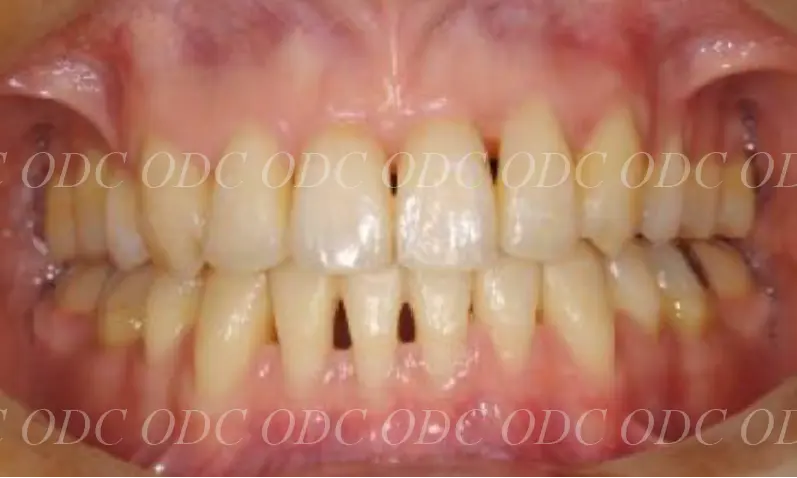

2014年、治療終了時の口腔内の状態です。

インプラント上部構造はCADCAMによって作成されたジルコニアの上部構造です。

2024年、治療終了後約10年が経過いたしました。

顎関節を考慮した包括的な治療を行うことで咬合状態(噛み合わせ)は現在もとても安定した状態です。